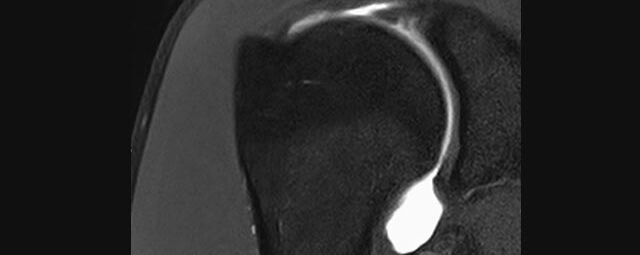

Gelenke

Hand

• Beurteilung von Knochen, Bändern und anderen Weichteilstrukturen der Gelenke nach Unfall.

• Arthrosediagnostik (Knorpelschaden)

• Impingement-Symptomatik

• Ursachenklärung bei wiederholter spontaner Gelenkluxation

• Ausbreitungsdiagnostik bei Gelenkentzündung, z.B. im Rahmen von rheumatischen Grunderkrankungen

Arthrographie

• MR-Arthrographie – nach örtlicher Betäubung und gründlicher Desinfektion der Haut wird unter Lagekontrolle mit Röntgen-Durchleuchtung eine kleine Nadel in den Gelenkraum positoniert und darüber ein MR-taugliches Kontrastmittel in den Gelenkraum gespritzt. Danach wird die Nadel entfernt. Anschließend erfolgt die MRT des Gelenkes. Diese Methode stellt kleine anatomische Strukturen des Gelenkraumes verbessert dar, z.B. zur Therapieplanung vor Arthroskopie bei Sportverletzungen der Schulter oder Gelenkinstabilität.